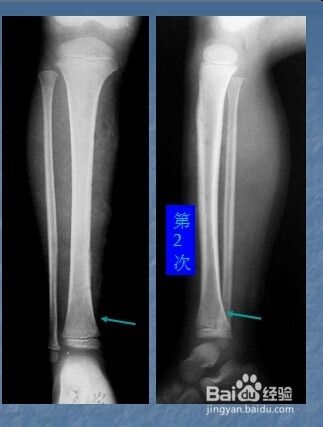

二:慢性化脓性骨髓炎X线。